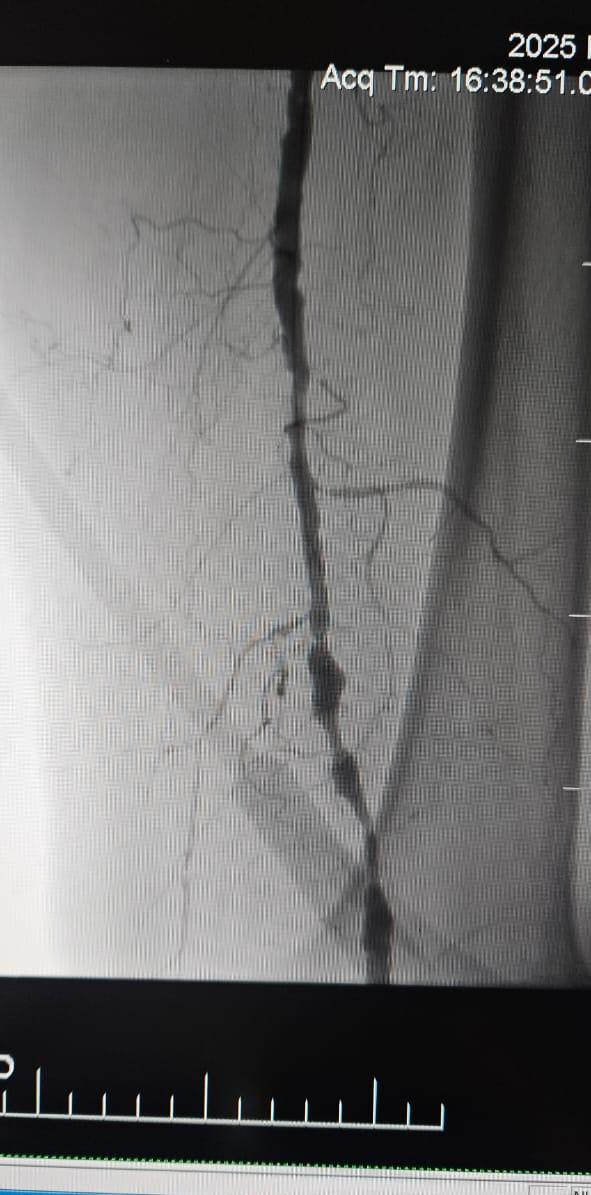

Alt ekstremite arterinin kronik toplam tıkanıklığının neden olduğu kritik uzuv iskemi (cli) olan 78 yaşındaki bir kadın hastanın torçatlak periferik ivl balon dilatasyon kateter sistemi ile tedaviyi takiben dikkat çekici bir klinik iyileşme gösterdiği batum, gürcistan'daki bir hastaneden başarılı bir davayı paylaşmaktan memnuniyet duyuyoruz.

Bu durum, uzun segmentli kronik tıkanıklığa sahip karmaşık cli vakalarının tedavisinde intravasküler litotripsinin (ivl) klinik değerinin altını çizmektedir-özellikle geleneksel balonların veya atherektomi cihazlarının sınırlı etkinliğe sahip olduğu ağır kalsifikasyon olan hastalarda.